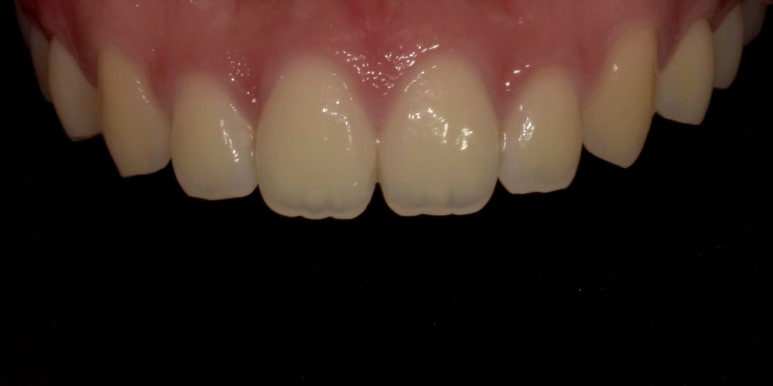

잇몸성형 전후 사진

(전) 2023-05-13 (후) 2023-05-26

위 환자분은 잇몸라인이 다소 평평해보여 라운드하고 고른 라인을 만드는데 중점을 두었습니다.